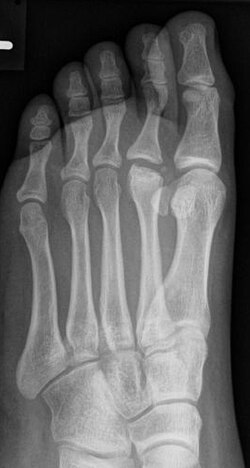

Der betroffene Vorfuß schmerzt bei Belastung, gelegentlich treten auch Schwellungen am Fußrücken im Bereich des Mittelfußköpfchens auf. Im Röntgenbild zeigen sich erst eine Veränderung in der Knochenstruktur des betroffenen Mittelfußköpfchens und erst später eine Abflachung und eine Verbreiterung (siehe Abbildung). Auf Dauer kann die Fehlform der Mittelfußköpfchens zu einer Arthrose führen.

| Morbus Freiberg-Köhler | Praxis Dr. Jochen Lengerke | Dr. Jochen Lengerke | Datei:Morbus Köhler-Freiberg.jpg | |